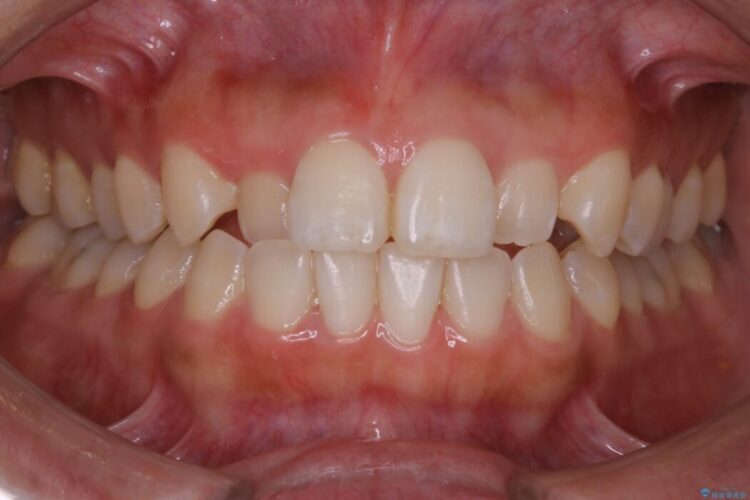

反対咬合の歯も整ったアーチに収まり、きれいに仕上がりました。

今回のケースでは前歯部の軽い凹凸のみであったため部分矯正の適応範囲に該当していました。